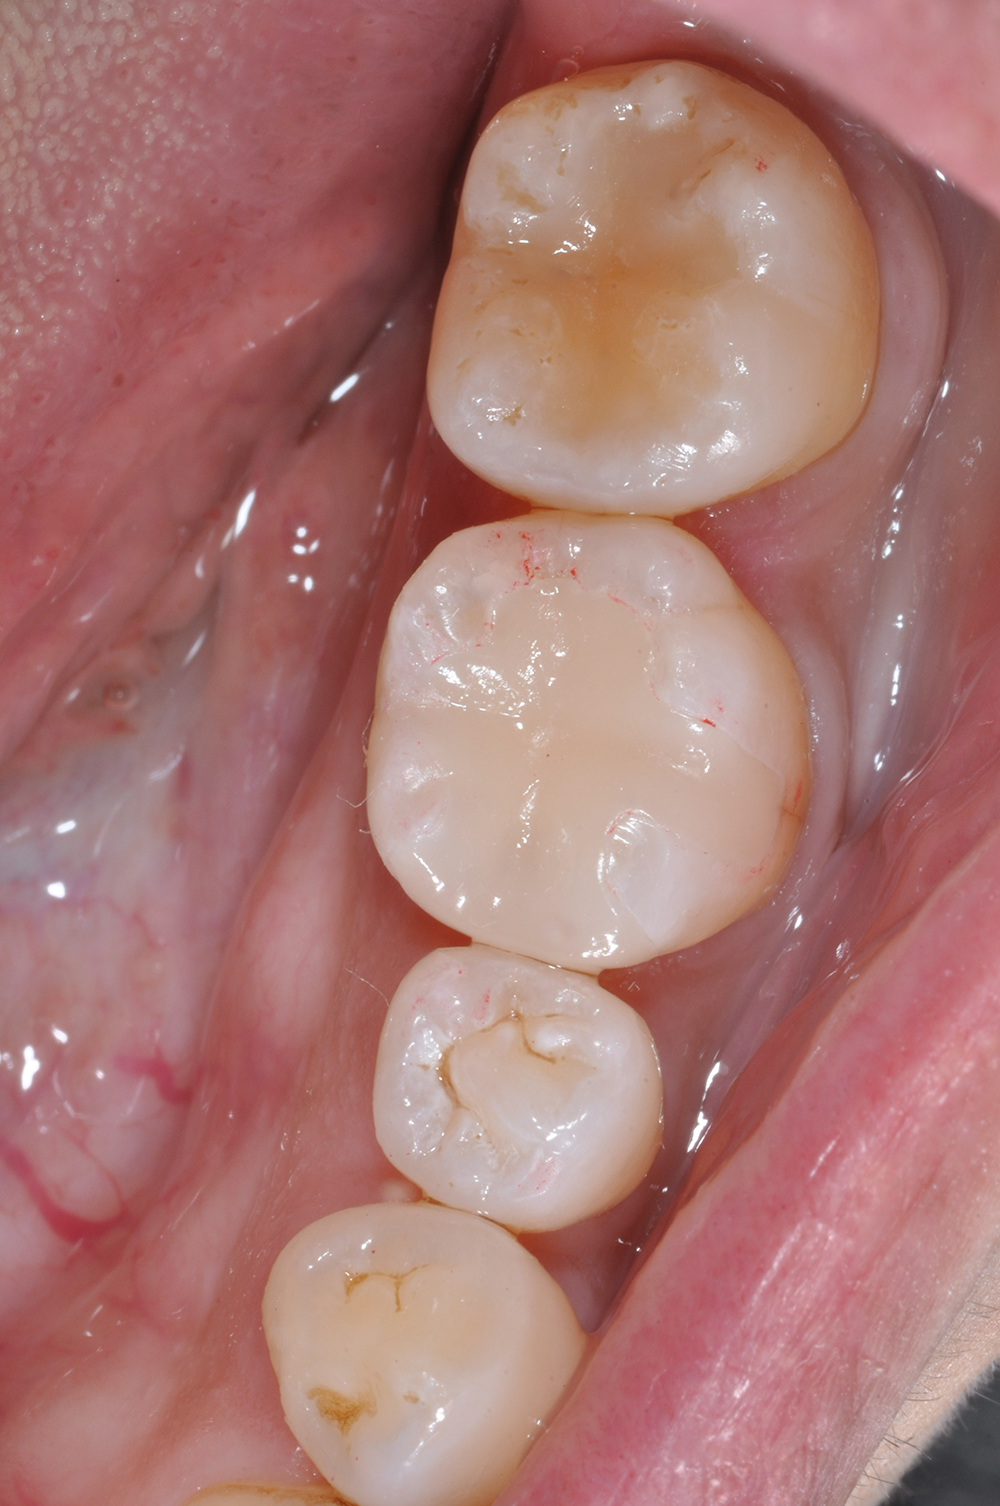

術前

術後

世代・性別

40代女性

主訴

ずっと痛い、噛むと特に痛い、前医でもうこれ以上はできないと言われた

治療内容

根管治療

治療期間

2ヶ月

治療費

保険適応内

治療のリスク

治療中または治療後に、一時的な痛みや腫れが生じることがある